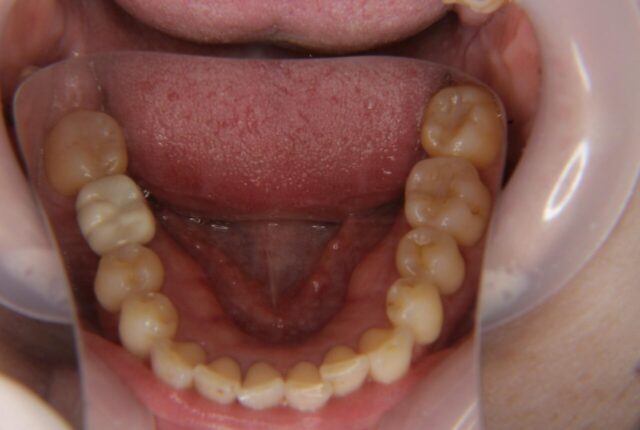

Before

| 主訴 | 歯牙の破損 |

| 年齢 | 30代 |

| 性別 | 女性 |

| 治療期間・回数 | 5ヶ月 7回 |

| 治療方法 | インプラント治療 |

| デメリット・注意点 | きれいな歯を削らず長期間保存するため、インプラント治療を選択。 |

| 備考 | 治療前後ではなく、長期間安定しているインプラント症例の紹介です。 定期メンテナンスに来ていただき、12年3ヶ月の間、問題なくお過ごしいただいてます。 歯を削ることなく治療が完了しており、インプラントだけではなくお口全体がとてもきれいな状態を維持できています。 |